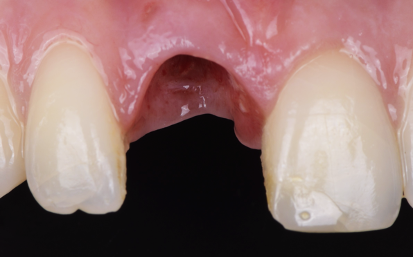

Elle se présente alors en consultation parce qu’elle a entendu un « crack » en mangeant un aliment. Elle relate depuis des douleurs persistantes et une légère mobilité de la dent. L’examen clinique et radiologique révèle une fracture palatine au niveau du tiers cervical radiculaire qui est sous osseuse, rendant la dent non conservable.

Extraction de la dent la plus atraumatique possible (Photo 10).